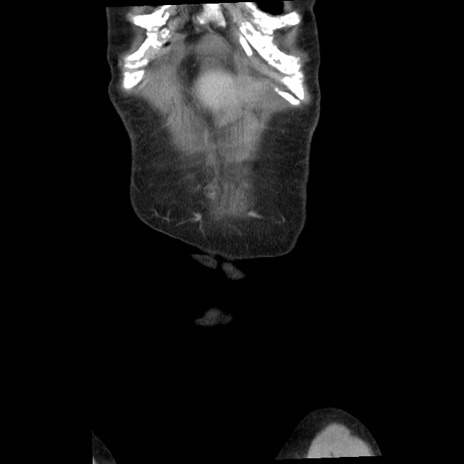

矢状断像

【症例】80歳代女性

【主訴】腹痛

【現病歴】8時間前から腹痛あり来院。

【既往歴】糖尿病、脂質異常症、子宮体癌にて子宮全摘術

【身体所見】意識清明・会話良好だが腹痛で苦悶様、全腹部にわたって反跳痛と圧痛あり

【データ】WBC 13600、CRP 0.14、LDH 224、CK 90